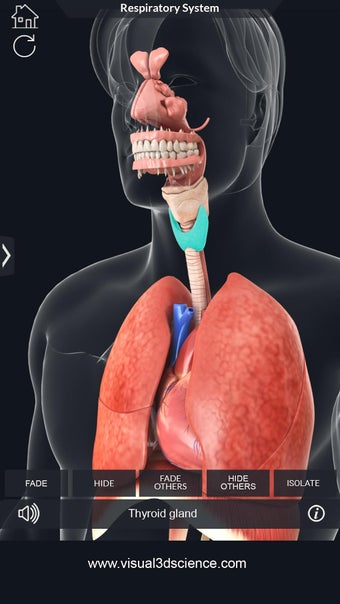

呼吸器系の解剖学は、肺、気管、およびすべての気道を含む呼吸器系の解剖学の研究です。最も一般的なアプローチは、系を上部と下部に分割することです。上部には気管、主気管支、および終末および前頸気道が含まれます。下部には肺と最小の大きさの末梢気道が含まれます。これらの部分それぞれには特徴的な外観と機能があります。

このアプリケーションは、高度にリアルな呼吸器系のモデルです。ユーザーは任意の角度および任意の平面から呼吸器系の解剖学を表示できます。ユーザーは360°回転し、ズームインおよびズームアウトして解剖学をよりよく研究することができます。ユーザーはまた、画面に描画するためのさまざまなツールを使用して写真を撮ることもできます。